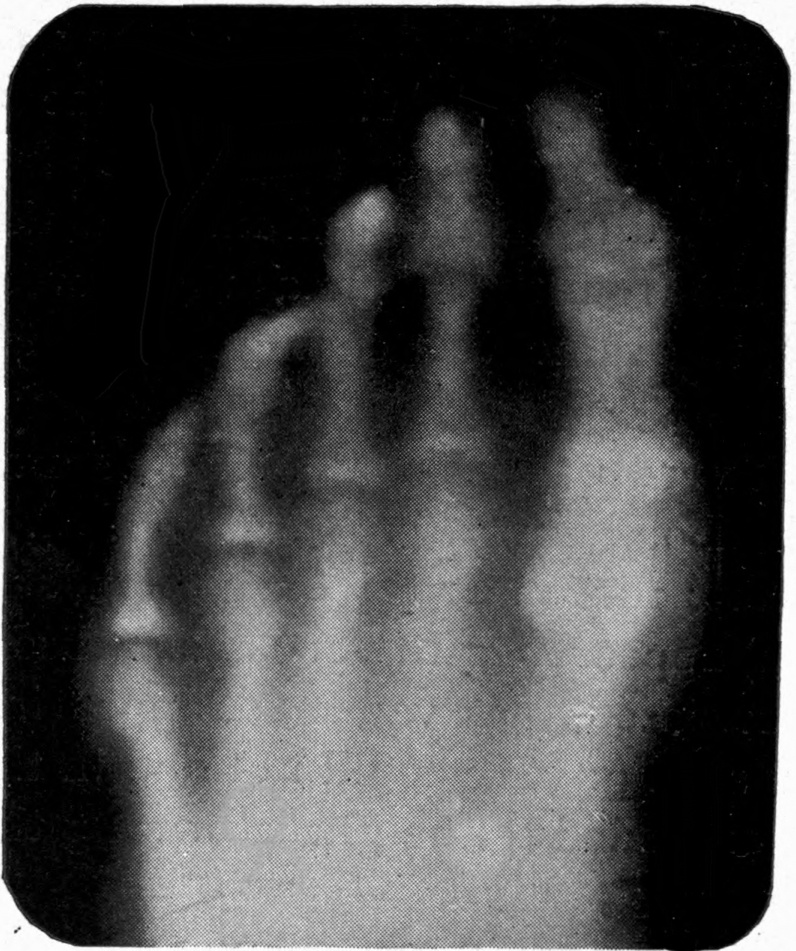

Fig. 2.—Broken Arm, Overlapping.

(Due to defective setting.)

Fig. 3.—Ribs.

Fig. 4.—Knee, Knickerbocker Buttons, Bullet in Femur.

FROM SCIAGRAPHS BY PROF. DAYTON C. MILLER. § 204.